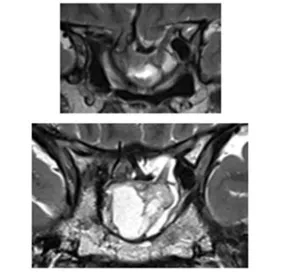

咨詢到神經(jīng)外科后,經(jīng)過核磁共振檢查后原來小葵腦子里長了一個垂體泌乳素瘤(圖1)!小葵之所以會出現(xiàn)嚴重的視力下降,就是因為腫瘤已經(jīng)壓迫到了視神經(jīng),而隨著腫瘤的持續(xù)增長,小葵很可能遠遠失去視力……

侵襲性垂體瘤實例交流——病灶圖片

圖1:初始病灶